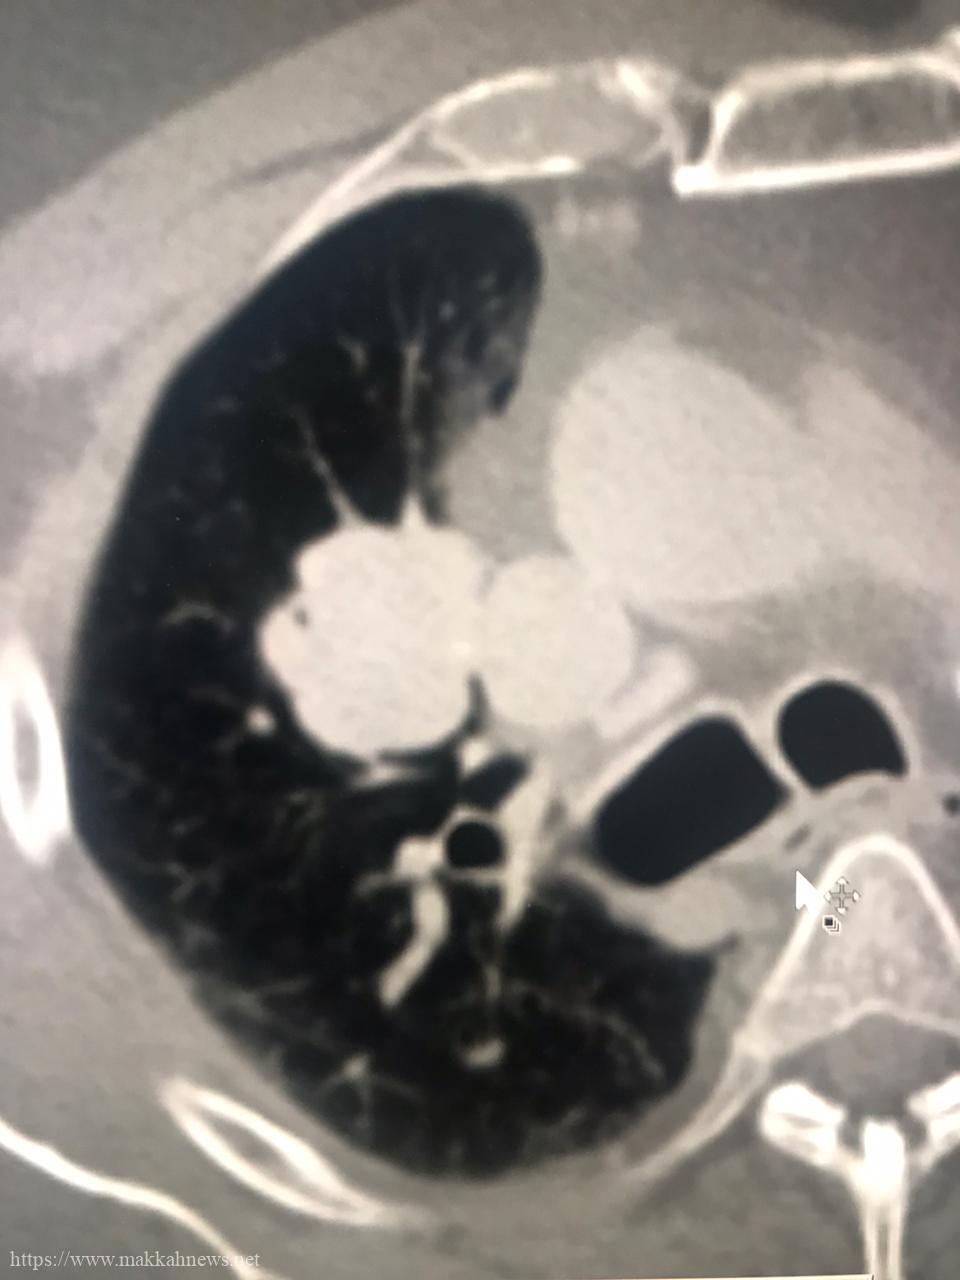

الاشعة التداخلية بطبية مكه تنهي معاناة خمسيني من ورم ممتد بالرئه بتقنية المايكروويف الموجه

نجح فريق طبي بمدينة الملك عبدالله الطبية بالعاصمة المقدسة ممثلا بقسم الاشعة التداخلية بفضل من الله من إنهاء معاناة مريض…